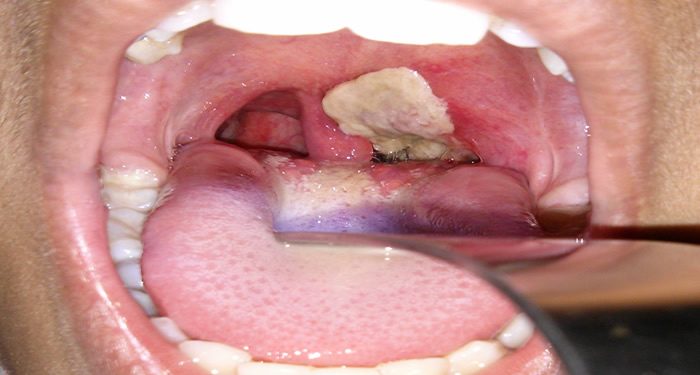

Diphtheria is a serious bacterial infection caused by the bacterium called Corynebacterium species that affects the nose, throat, and sometimes, skin of an individual.